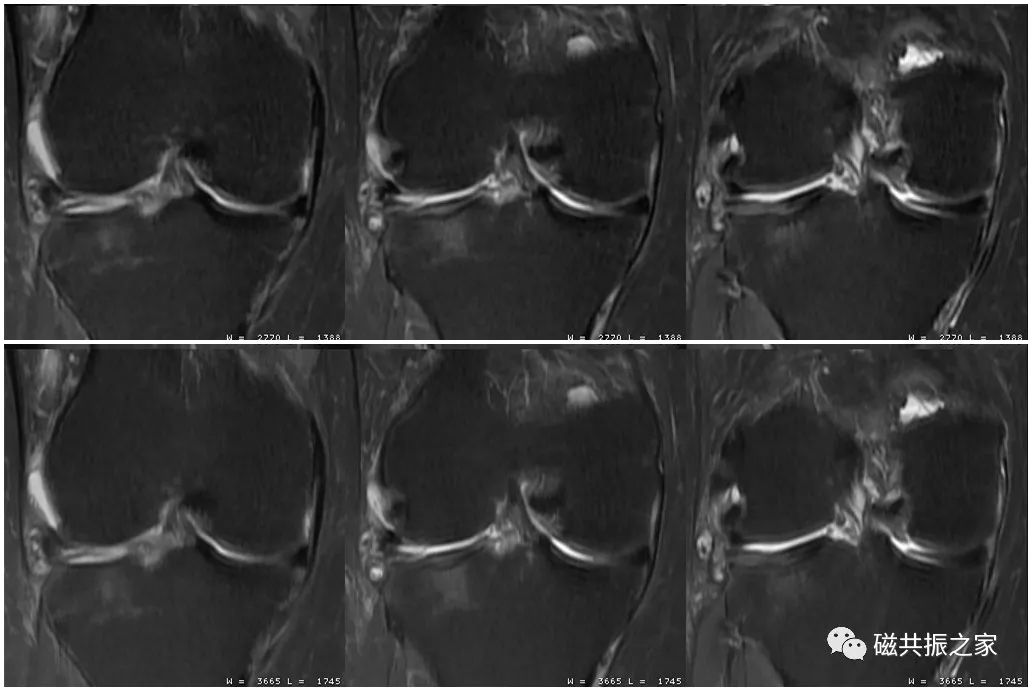

图像的分辨率并不是由单一参数决定的,在调整参数时应综合考虑时间、信噪比、对比度、伪影等相关因素。如图,上1,2,3幅图像的频率编码数为320;下1,2,3幅图像的频率编码数为512;虽然下面三幅图像的扫描体素较上面三幅图像更小,理论上分辨率会更高,但其实际分辨率并不及上面三幅图像。